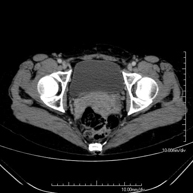

- TC Pelvis Prueba diagnóstica que consiste en obtener imágenes bi y tridimensionales de la pelvis de alta definición anatómica (estructuras óseas, estructuras vasculares, vejiga, útero y ovarios, próstata y vesículas seminales, uréteres, etc.) mediante el empleo de un equipo de TC (Tomografía Computarizada). La mayoría de estudios requieren el empleo de contraste yodado. Prueba diagnóstica que consiste en obtener imágenes bi y tridimensionales de la pelvis de alta definición anatómica (estructuras óseas, estructuras vasculares, vejiga, útero y ovarios, próstata y vesículas seminales, uréteres, etc.) mediante el empleo de un equipo de TC (Tomografía Computarizada). La mayoría de estudios requieren el empleo de contraste yodado.

- TC Abdominopélvico Prueba diagnóstica que consiste en obtener imágenes bi y tridimensionales del abdomen y de la pelvis de alta definición anatómica (estructuras óseas, estructuras vasculares, hígado, páncreas, vesícula biliar, riñones, glándulas suprarrenales, bazo, intestino delgado y grueso, vejiga, útero y ovarios, próstata y vesículas seminales, uréteres, etc.) mediante el empleo de un equipo de TC (Tomografía Computarizada). La mayoría de estudios requieren el empleo de contraste yodado. Prueba diagnóstica que consiste en obtener imágenes bi y tridimensionales del abdomen y de la pelvis de alta definición anatómica (estructuras óseas, estructuras vasculares, hígado, páncreas, vesícula biliar, riñones, glándulas suprarrenales, bazo, intestino delgado y grueso, vejiga, útero y ovarios, próstata y vesículas seminales, uréteres, etc.) mediante el empleo de un equipo de TC (Tomografía Computarizada). La mayoría de estudios requieren el empleo de contraste yodado.